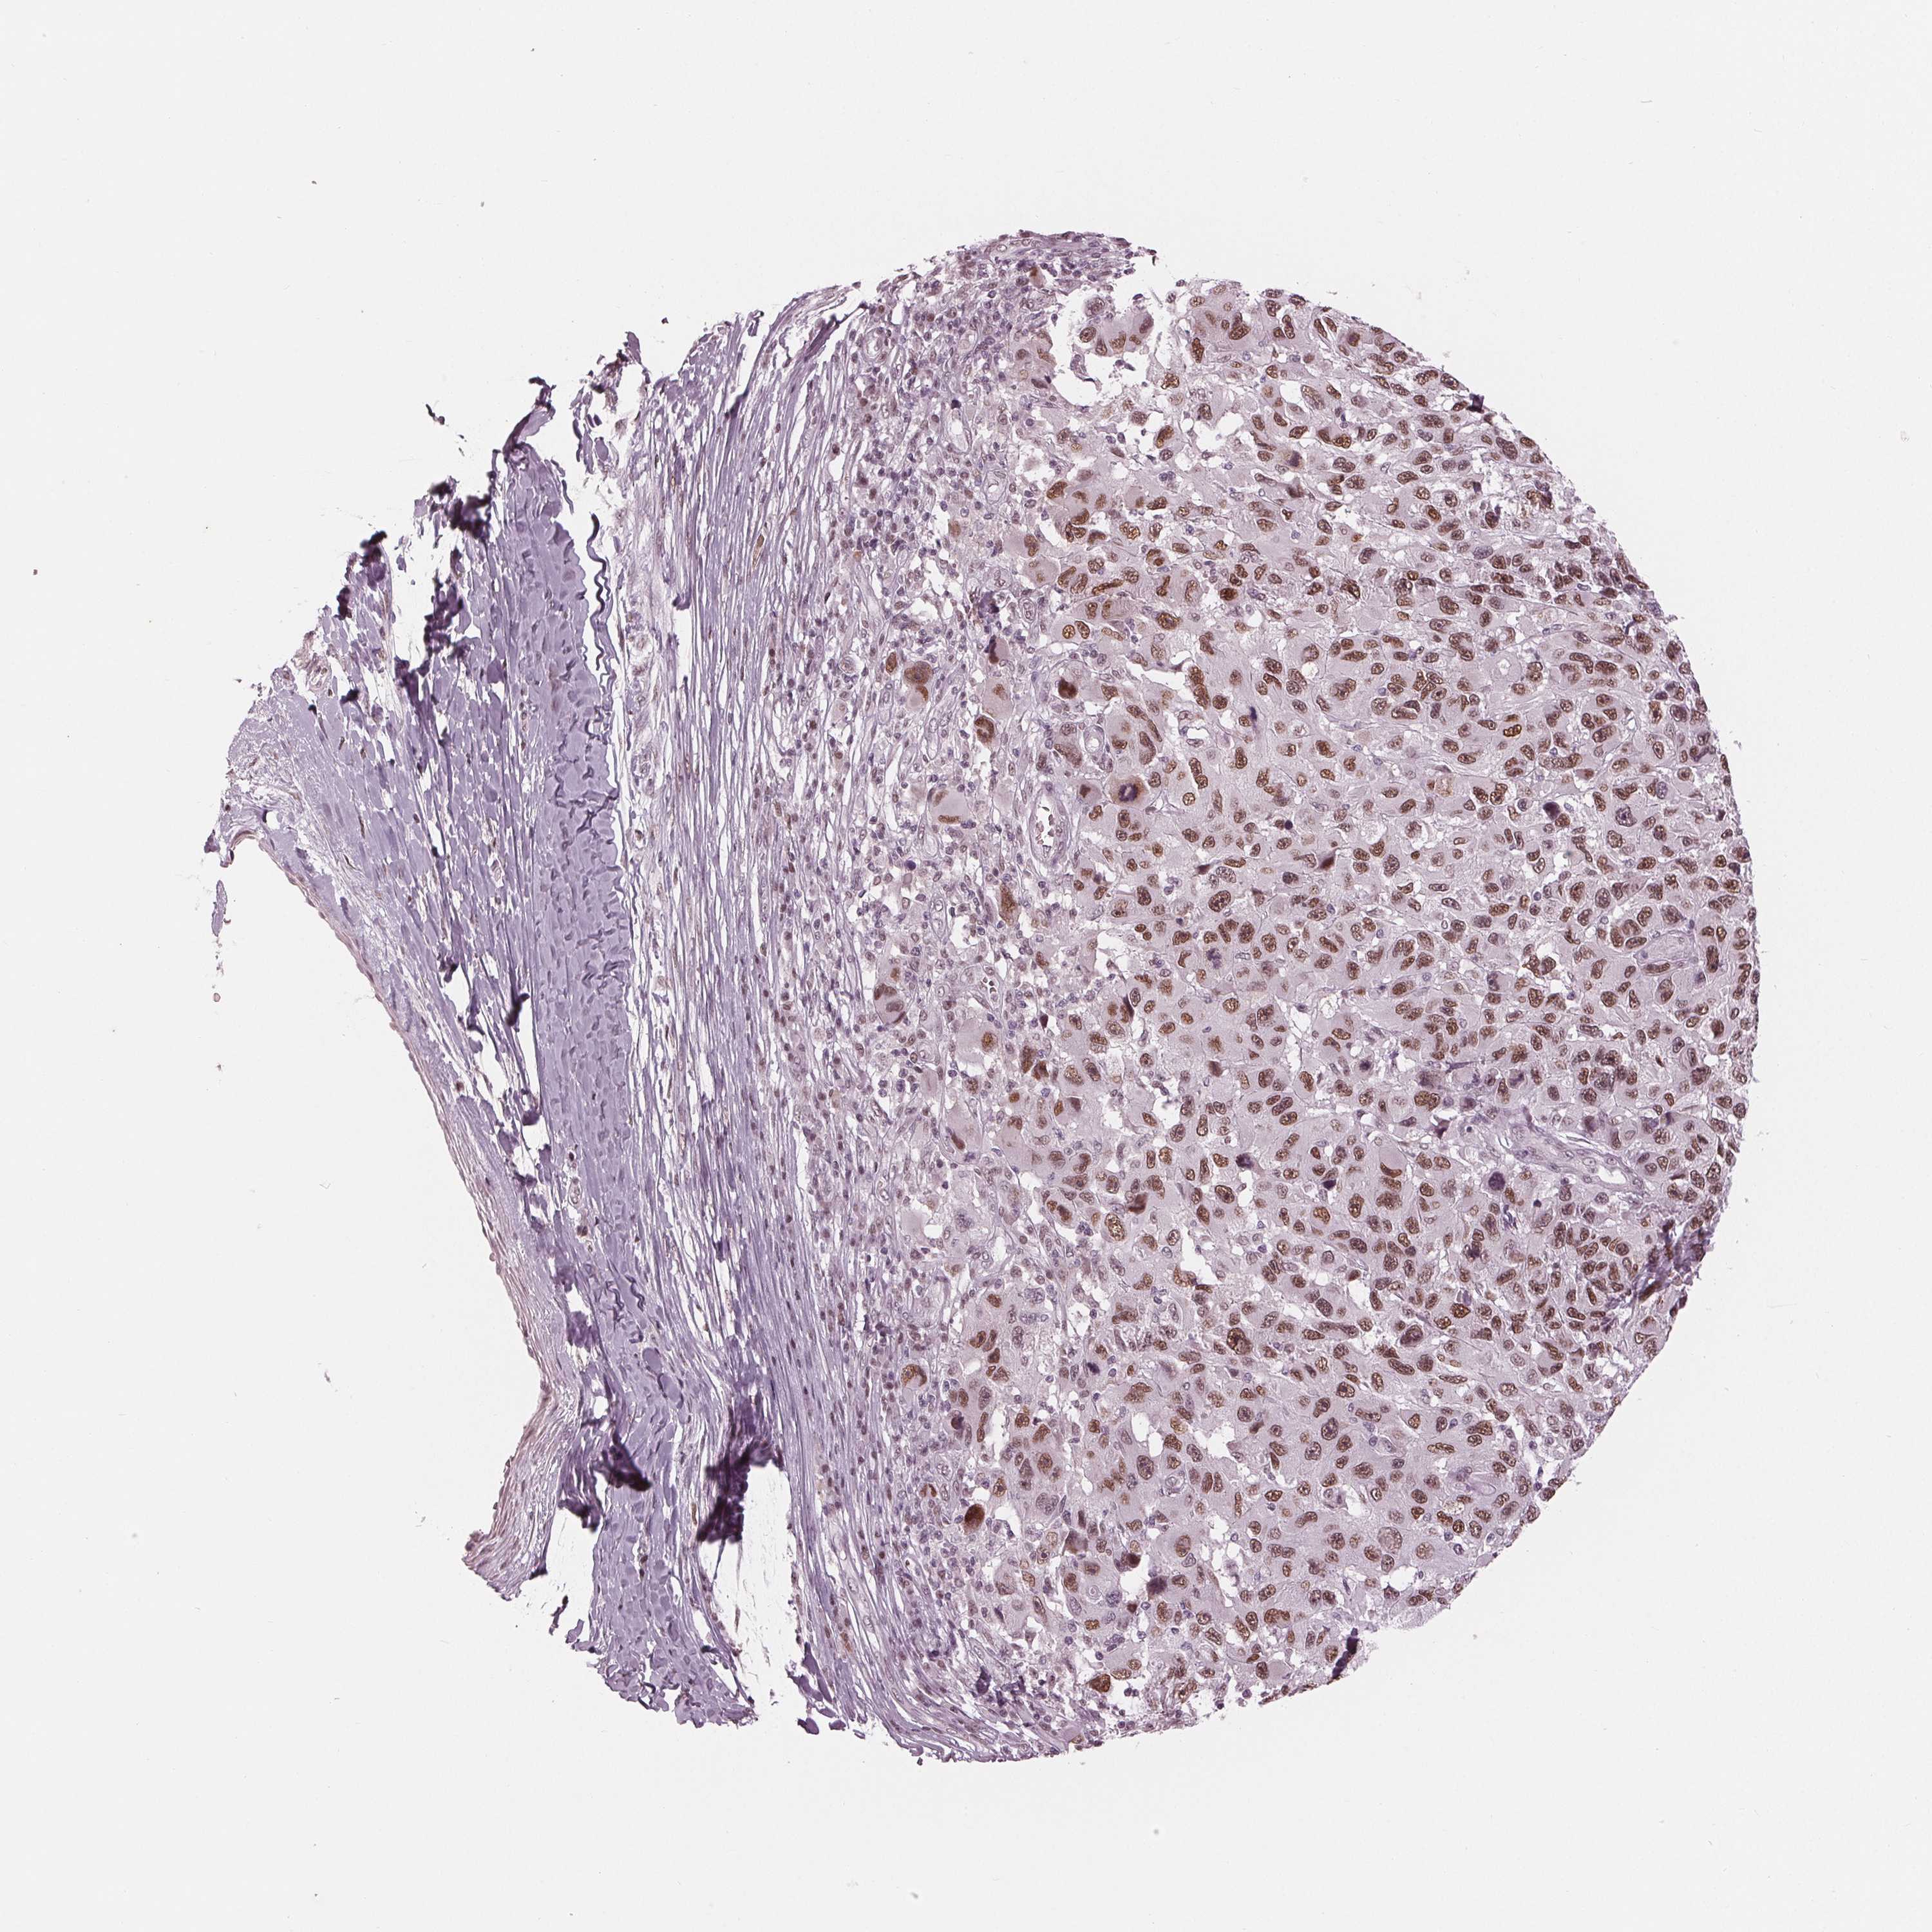

MELANOMA - Protein expressioni

A mouse-over function shows sample information and annotation data. Click on an image to view it in a full screen mode. Samples can be filtered based on level of antibody staining by selecting one or several of the following categories: high, medium, low and not detected. The assay and annotation is described here.

Note that samples used for immunohistochemistry by the Human Protein Atlas do not correspond to samples in the TCGA dataset.

Antibody stainingi

Antibody staining in the annotated cell types in the current human tissue is reported as not detected, low, medium, or high, based on conventional immunohistochemistry profiling in selected tissues. This score is based on the combination of the staining intensity and fraction of stained cells.

Each image is clickable and will lead to virtual microscopy that enables deeper exploration of all samples and also displays staining intensity scores, fraction scores and subcellular localization as well as patient and tissue information for each sample.

Antibody HPA066780

Staining

High

Medium

Low

Not detected

Intensity

Strong

Moderate

Weak

Negative

Quantity

>75%

75%-25%

<25%

None

Location

Nuclear

Cytoplasmic/membranous

Cytoplasmic/membranous,nuclear

Malignant melanoma, NOS

Malignant melanoma, Metastatic site